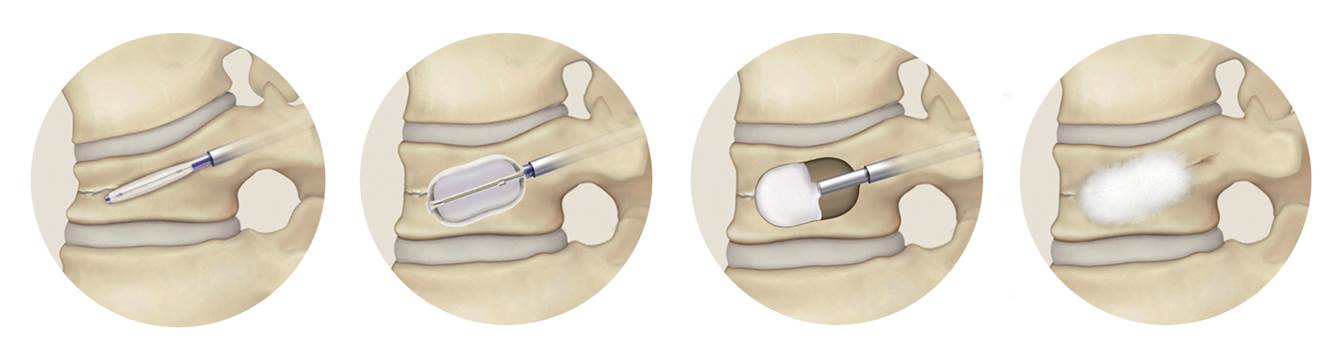

BKP Balloon Kyphoplasty 【バルーン カイフォプラスティ】

骨粗鬆症による圧迫骨折や転移性脊椎腫瘍などによる長期につづく痛みで、一般的な鎮痛薬やコルセットなどの治療で軽快しない腰痛に対して行なわれます。

- 全身麻酔で1時間程度の手術です。

- 背中に2箇所、7mm程度の切開をおきます。

- 風船(バルーン)を使って潰れた椎体を持ち上げます。

- 風船(バルーン)を抜き、出来た空間に骨セメントを充填します。

平成24年の保険診療改正によりBKP手術は「経皮的椎体形成術」として正式な手術として認められました。BKPの手術は認定資格が必要で、認定病院での手術実習を受講し、試験に合格した医師のみが施行できます。当院では本手術が施行可能ですが、骨折の状態や時期など、適さない場合がありますので担当医にご相談ください。